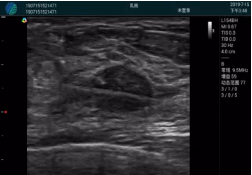

腺體內(nèi)部清晰顯示一低回聲塊影,形態(tài)不規(guī)則,邊界模糊,邊緣呈毛刺狀,內(nèi)部見砂礫樣鈣化

M20引導(dǎo)下穿刺活檢術(shù)